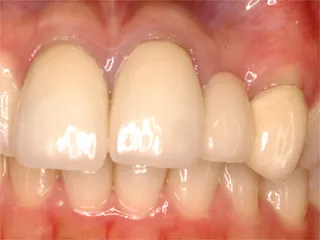

| 自費ブリッジ |

保険のブリッジ

|

通常のブリッジは 強度を維持するため大きくなります メタルボンドは 適正なサイズで色も自然です ■長所 ・金属が見えない ■短所 ・前後の歯を削り犠牲にする ・高い |